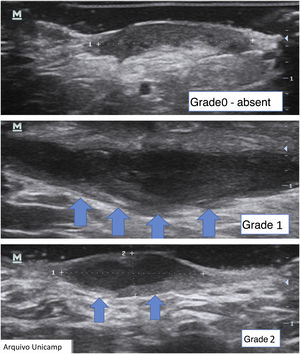

Another important complementary assessment is the grading of fibrosis (Fig. 11),16 which may appear as absent (grade 0), as a thin peripheral hypoechoic band with a fibrillar pattern (grade 1) or as a thick, peripheral hypoechoic band with a fibrillar pattern that invades the fistula lumen and produces a hypoechoic halo that is transversely visible (grade 2).

A fistula with a high degree of fibrosis is chronic and requires surgical treatment.